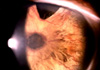

潛伏期1-3d,兩眼同時或相隔1-2d發病。發病3-4d時病情達到高潮,以後逐漸減退。表現為患眼紅、燒灼感,或伴有畏光、流淚。結膜充血,中等量粘膿性分泌物,夜晚水面後,上下瞼睫毛常被分泌物粘合在一起。視力一般不受影響,如分泌物附於角膜表面時,可致一過性視力模糊或虹視。病情較重者可出現結膜下出血。肺炎球菌、流感嗜血桿菌Ⅲ型(Koch-Weeks桿菌)所致結膜炎,可在瞼結膜表面覆蓋一層假膜。流感嗜血桿菌Ⅲ型感染處還可並發卡他性邊緣性角膜侵潤或潰瘍。部分患者伴有體溫升高、身體不適等全身症狀。